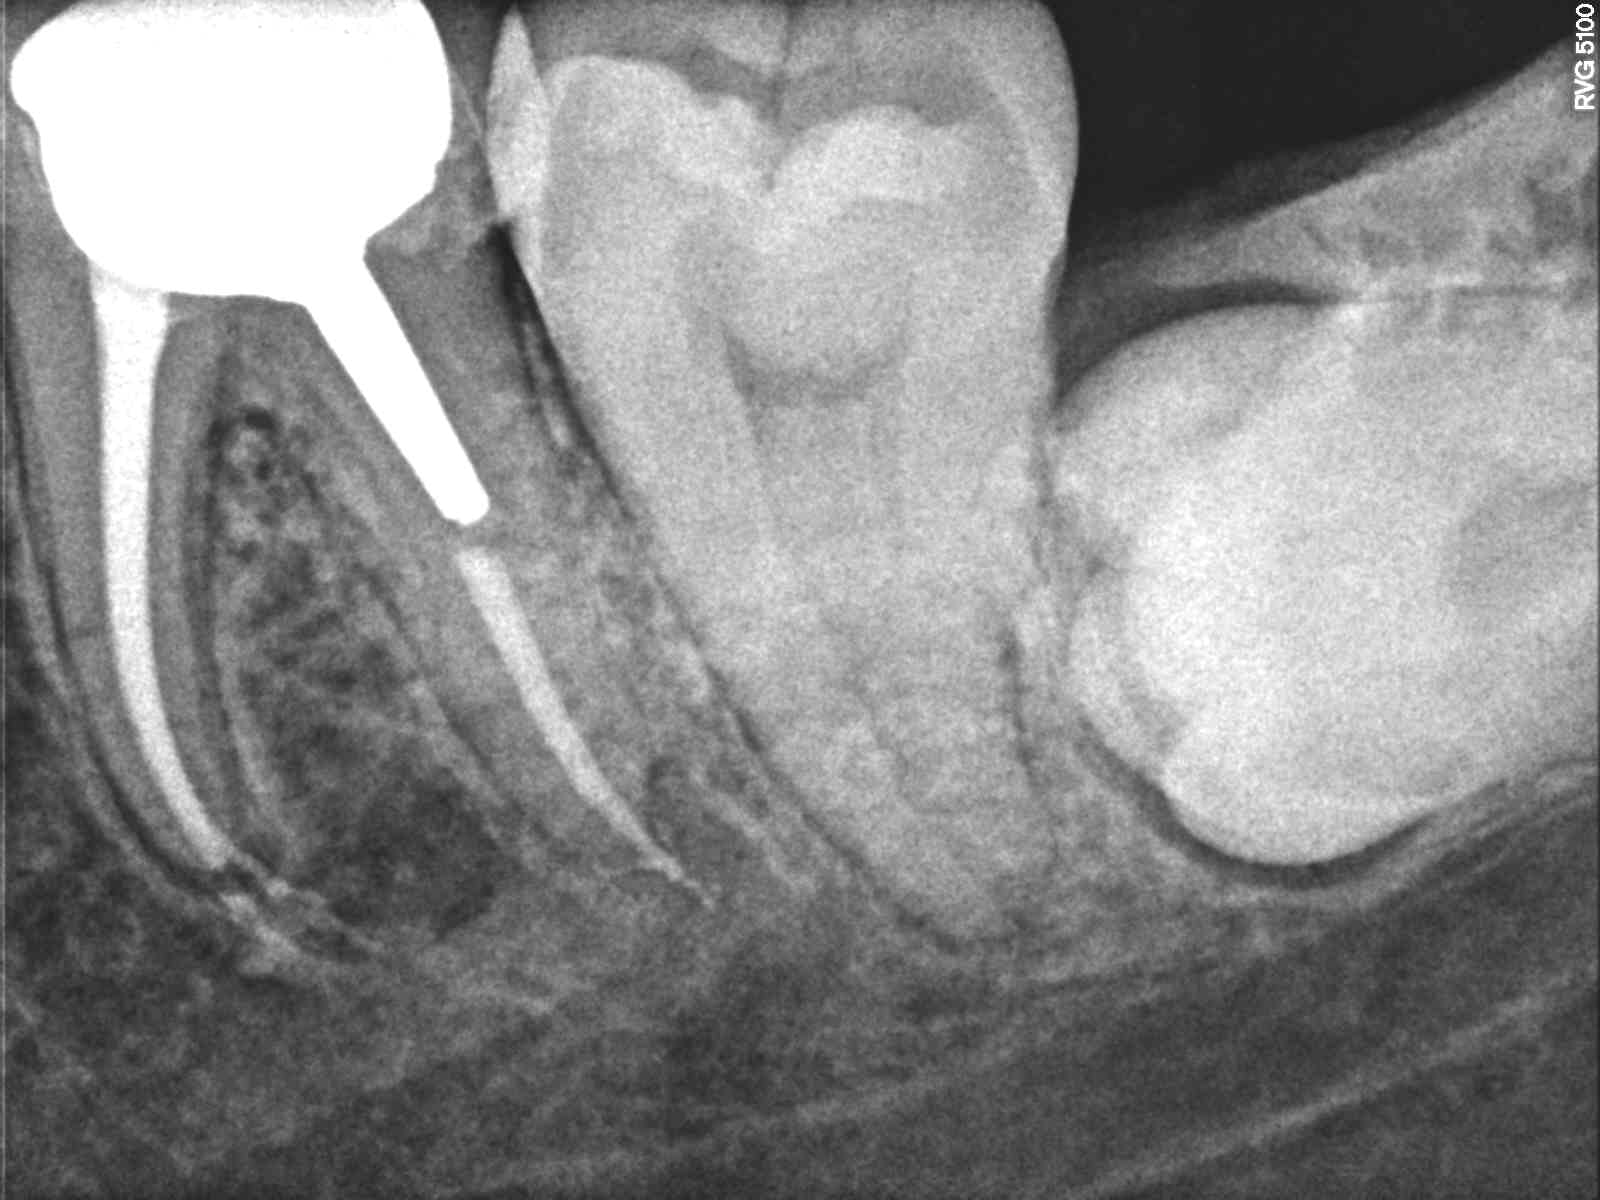

Sur la dernière radio on voit un épaississement.

Dépassement gutta en distal ?

J'avais surinstrumenté en mésial et distal le ciment a fusé dedans.

c'est ce que je vois aussi et l'épaississement en mésial visible sur la dernière radio fait suite à ce trait.

Dépose de l'inlay core et microscope.

Un scanner?!